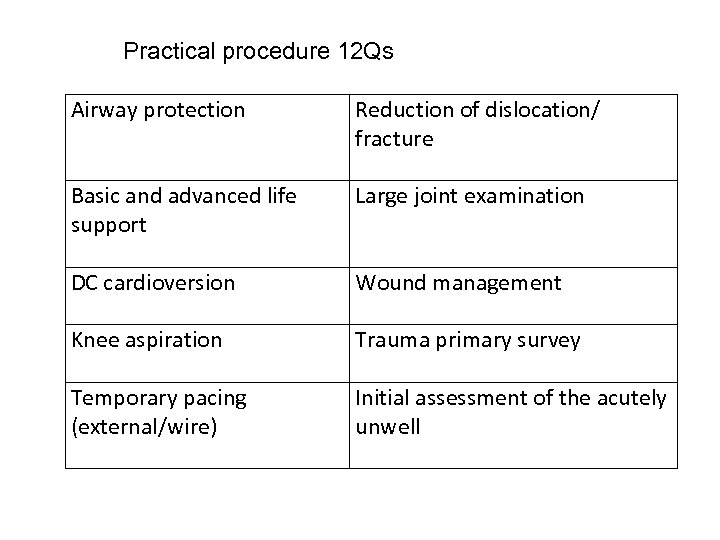

Practical procedure 12 Qs Airway protection Reduction of dislocation/ fracture Basic and advanced life support Large joint examination DC cardioversion Wound management Knee aspiration Trauma primary survey Temporary pacing (external/wire) Initial assessment of the acutely unwell